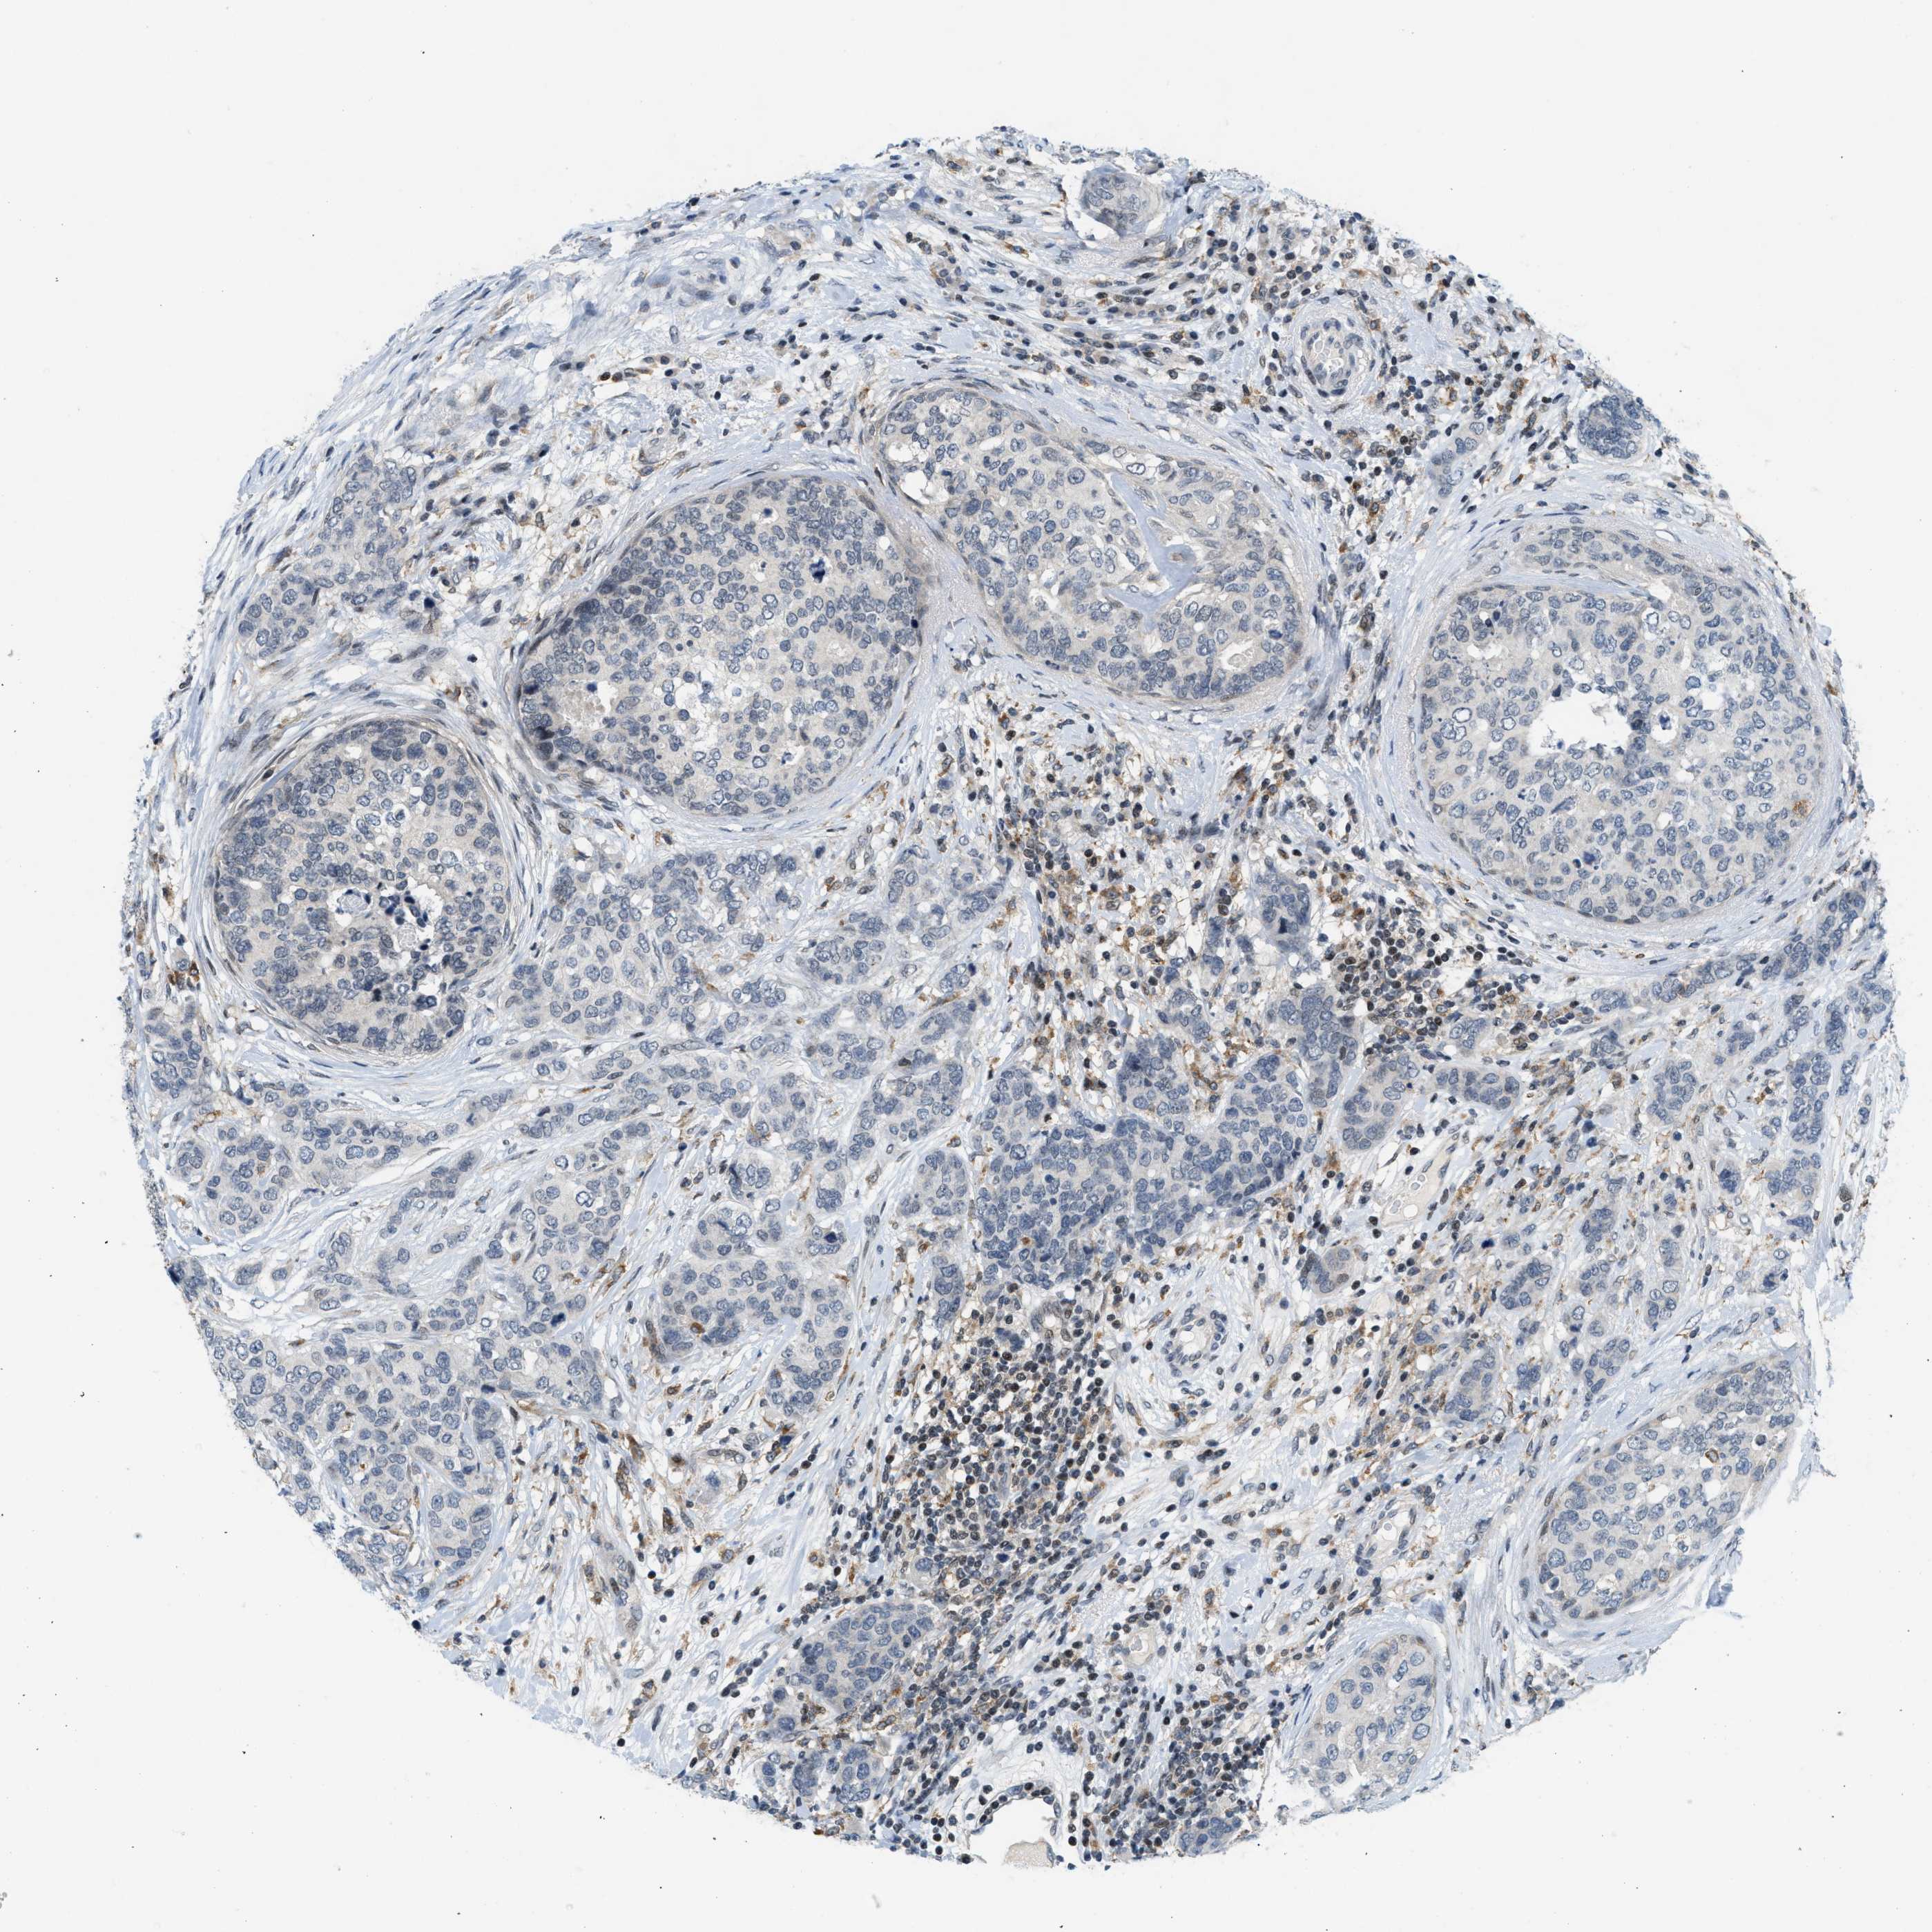

CANCER BREAST CANCER Show tissue menu

BRCA TCGA BRCA VALIDATION PROTEIN EXPRESSION

ANTIBODIES

AND

VALIDATION